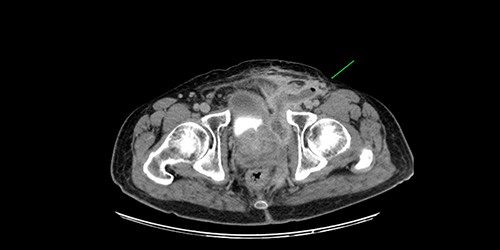

A 61-year-old diabetic patient was admitted from emergency department with septic signs; fever of 39°C, white blood cell count of 20.000/μl, C-reactive protein levels of 156 mg/l and blood glucose levels of 280 mg/dl. For the past 10 days, the patient has noted malodorous anorectal pus discharge, as well as anorectal and suprapubic pain. During macroscopic examination of the perineum, a left-sided abscess in the ischiorectal fossa was identified, with an opening lateral to the sphincteric anal system draining pus. Subsequent digital rectal examination of the anorectal canal could not be completed due to pain, but the initial effort revealed large amounts of pus discharged from anorectal canal. CT and MRI demonstrated an abscess situated in the left ischiorectal fossa and a large supralevator abscess extending cephalad in the extraperitoneal space with a long fistulous tract containing liquid (pus) and gas bubbles, up to the suprapubic area, where erythema with an undulating pus collection below the skin was noted; laterally the pus collection extended up to the left ilio-femoral vessel canal. CT (Fig. 1) and MRI (Fig. 2) were conclusive for the above entity, aptly demonstrating the presence of the two abscess cavities. Proctoscopy under general anesthesia revealed a protruding extra-rectal mass in the left lateral and inferior segment of the rectal ampulla. Finger pressure at this point was accompanied with pus exit from the posterior dentate line of the anal canal at 6 o’clock, through an opening of 1–2 mm in size. Surgery was addressed in three main locations of the pus collection with goal to drain completely the pus; the abscess of the left ischiorectal fossa was drained with enlargement of the external opening of fistula; after curettage, debridement and washing of abscess cavity, a probe was used to detect the internal opening exactly at the posterior dentate line at 6 o’clock. The fistula was characterized as full trans-sphincteric with an extra-sphincteric component in the ischiorectal fossa leading up to the skin. A non-cutting vessel loop drainage seton was then placed. The supralevator abscess was then easily drained from the opening in the posterior dentate line by finger pressure in the left rectal ampulla. A probe following the route of the internal opening upwards to supralevator space led to pus evacuation, allowing this space to be thoroughly washed with water saline solution, using a syringe with a vein catheter. Finally, the suprapubic area was drained with a small stab incision, followed by washing with normal saline. There was a prompt recovery postoperatively, tight control of blood glucose levels, whereas a CT performed 7 days postoperatively (Fig. 3), demonstrated an empty supralevator space with a fistulous tract still present, albeit with significant regression of inflammatory changes.

Postoperative CT of the lower pelvis, demonstrating a collapsed left supralevator space and superiorly expanding fistulous tract.